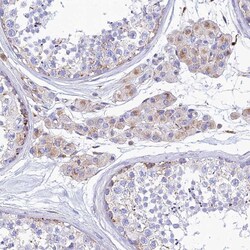

- Submitted by

- Invitrogen Antibodies (provider)

- Main image

- Experimental details

- Immunohistochemical analysis of SPNS1 in human testis using SPNS1 Polyclonal Antibody (Product # PA5-59813) shows weak granular cytoplasmic positivity in Leydig cells.